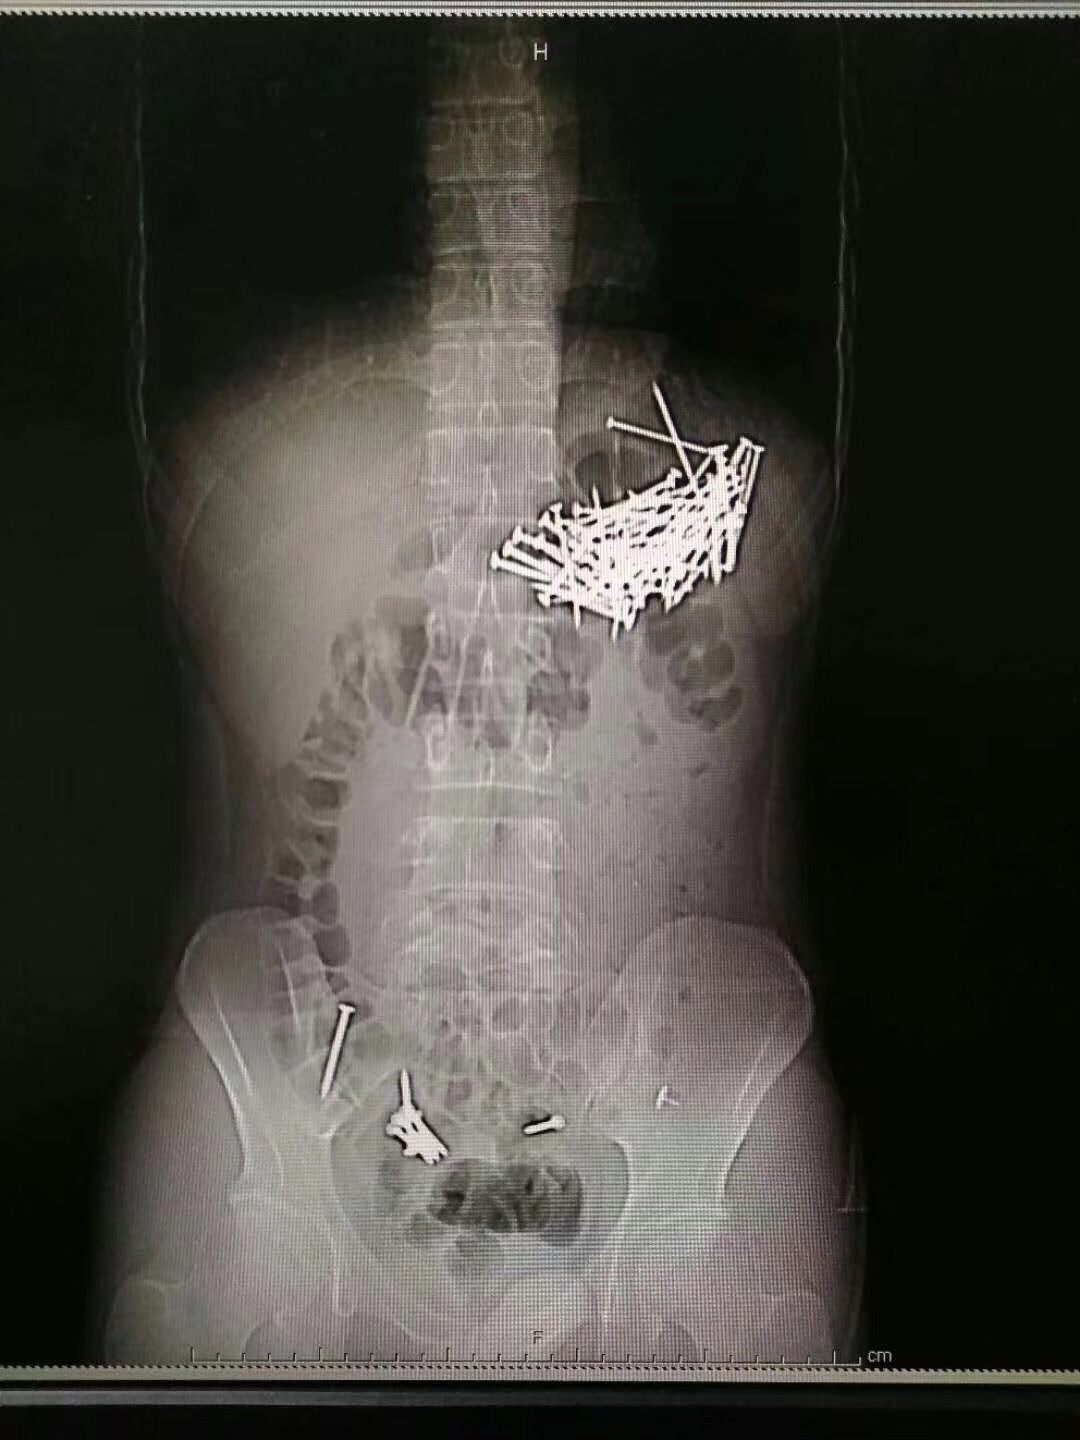

8月8日晚上,醫院接到求救信息,一個在北湖路某酒店居住的小夥子稱自己吃了包子後肚子疼痛難忍,需要醫生急救。120急救人員將其接到醫院後發現,小夥子所吃的包子餡有異常。“拍片之後可以看到,他的肚子內有大量釘子狀物體。”郴州市第一人民醫院一名值班醫護人員表示,在手術之前,小夥子交給醫生一封寫給女友的“遺書”,説是若找不到親屬,可以打電話給女友。

8月9日晚上7時許,聯繫到小夥子的親屬之後,醫院制定了手術方案並取得家屬同意,經過4個小時的忙碌,醫生從小夥子的腹腔和胃部等取出共87根鐵釘,每根釘子大約四五釐米長。“見過吞食異物的病人,但是沒有見過吞下這麼多釘子的病人。”一名醫護人員表示,小夥子自稱是吃了“釘子餡”包子,“肯定是一時想不開,才做了傻事,這可忙壞了我們連夜做手術的醫生,醒來之後我們得好好勸勸他。”

據手術醫生介紹,經過檢查和手術證實,這個小夥子吞食了87根鐵釘和7枚圖釘,其中6枚圖釘被病人自行排出,目前餘下一枚圖釘在直腸附近,由於體積較小,病人應該可以自行排出。